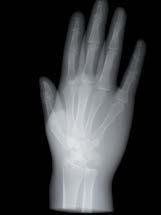

L’innovazione e la sicurezza sono due dei valori perseguiti dallo Studio Braconi a Terni, un punto di riferimento nell’ambito della radiologia 3D ortopedica grazie alla presenza del macchinario Newton 5G XL: si tratta dell’unico apparecchio nel Centro Italia che permette di eseguire una perfetta diagnostica per immagini in ortopedia e per la cervicale, oltre per le piccole articolazioni come seni paranasali, orecchie, colonna cervicale, gomito, polso, mano, ginocchio, caviglia e piede.

Nell’ambito della radiologia 3D ortopedica, il centro diagnostico utilizza il nuovissimo macchinario NewTom 5G XL, in grado di individuare con la massima precisione la presenza di fratture o lussazioni delle articolazioni, controllare la corretta guarigione di una frattura, valutare una lesione o una ferita causata da infezione, artrite o crescita anormale dell’osso.

Se con la radiologia tradizionale era necessario eseguire scansioni multiple, la novità introdotta dal macchinario NewTom 5G XL risiede nella capacità di fornire immagini ad alta risoluzione in un’unica scansione, mostrando nitidamente i dettagli delle articolazioni degli arti superiori e inferiori. Inoltre, a differenza della tecnologia 2D, la radiologia 3D ortopedica permette di individuare immediatamente alcune patologie come quella del metatarso, la quale richiede un allineamento visivo dedicato o una diagnosi delle micro fratture ossee.